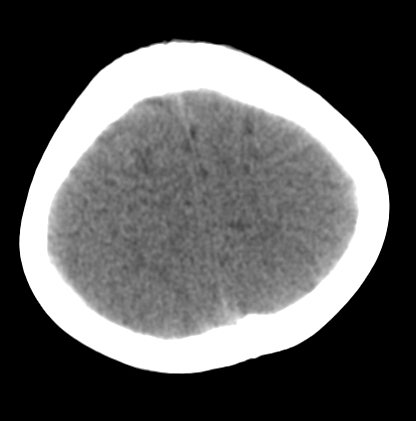

女,3岁,头部外伤一小时。半卵圆中心低密度是什么意思,病灶?侧脑室?请指教。

正常表现

幼儿正常脑白质表现,长期观察,必要时mr

不是侧脑室,考虑正常脑白质。为慎重,建议mr!